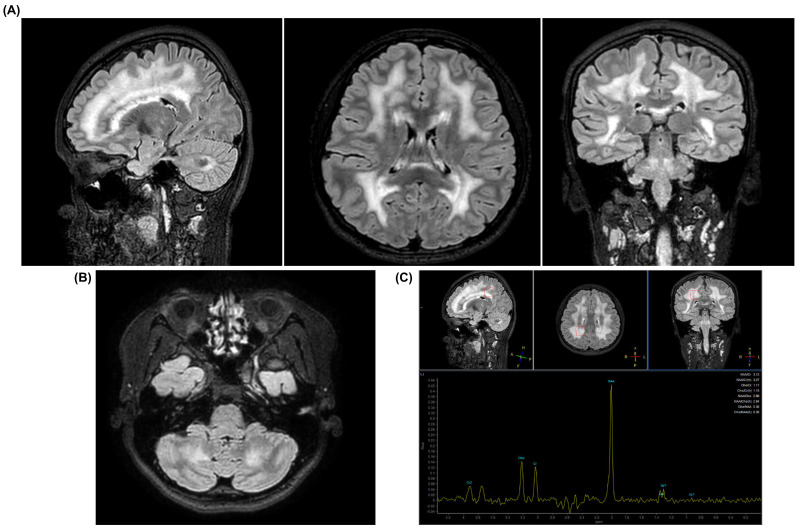

线粒体神经胃肠道脑肌病(MNGIE)是一种罕见的常染色体隐性遗传病,由TYMP基因突变引起,典型特征是严重和进行性胃肠道和神经系统表现。最近的报道已经确定了一组患者表现为全身性脂肪营养不良和代谢异常,这表明脂肪组织的累及可能是该疾病的一个未被认识的特征。在此,我们报告了一名16岁女性携带先前描述的TYMP纯合变体(c.1178_1201dup; p.Arg393_Val400dup)的病例,她在青春期表现为全身性脂肪营养不良、胰岛素抵抗、高甘油三酯血症、肝脂肪变性和其他代谢并发症。在诊断时,她没有表现出明显的神经或胃肠道症状;然而,神经电图显示亚临床周围神经病变。该病例通过记录与p.a arg393_val400dup变异相关的脂肪营养不良和代谢表现,拓宽了tymp相关疾病的表型谱。虽然TYMP突变在罕见的病例中与脂肪营养不良有关,但这种特定的变异以前只在经典的MNGIE背景下被报道过,没有脂肪组织或代谢紊乱的文献证据。我们的研究结果强调了考虑TYMP参与非典型脂肪营养不良综合征鉴别诊断的重要性,特别是当特征提示潜在的线粒体功能障碍时。

Mitochondrial neurogastrointestinal encephalomyopathy (MNGIE) is a rare autosomal recessive disorder caused by mutations in the TYMP gene, typically characterized by severe and progressive gastrointestinal and neurological manifestations. Recent reports have identified a subset of patients presenting with generalized lipodystrophy and metabolic abnormalities, suggesting that adipose tissue involvement may be an underrecognized feature of the disease. Herein, we report the case of a 16-year-old female carrying a previously described homozygous TYMP variant (c.1178_1201dup; p.Arg393_Val400dup), who presented during adolescence with generalized lipodystrophy, insulin resistance, hypertriglyceridemia, hepatic steatosis, and other metabolic complications. At diagnosis, she exhibited no overt neurological or gastrointestinal symptoms; however, electroneurography revealed subclinical peripheral neuropathy. This case broadens the phenotypic spectrum of TYMP-related disease by documenting a lipodystrophic and metabolic presentation associated with the p.Arg393_Val400dup variant. While TYMP mutations have been linked to lipodystrophy in rare cases, this specific variant had previously been reported only in the context of classical MNGIE, with no documented evidence of adipose tissue or metabolic derangement. Our findings highlight the importance of considering TYMP involvement in the differential diagnosis of atypical lipodystrophy syndromes, particularly when features suggest underlying mitochondrial dysfunction.